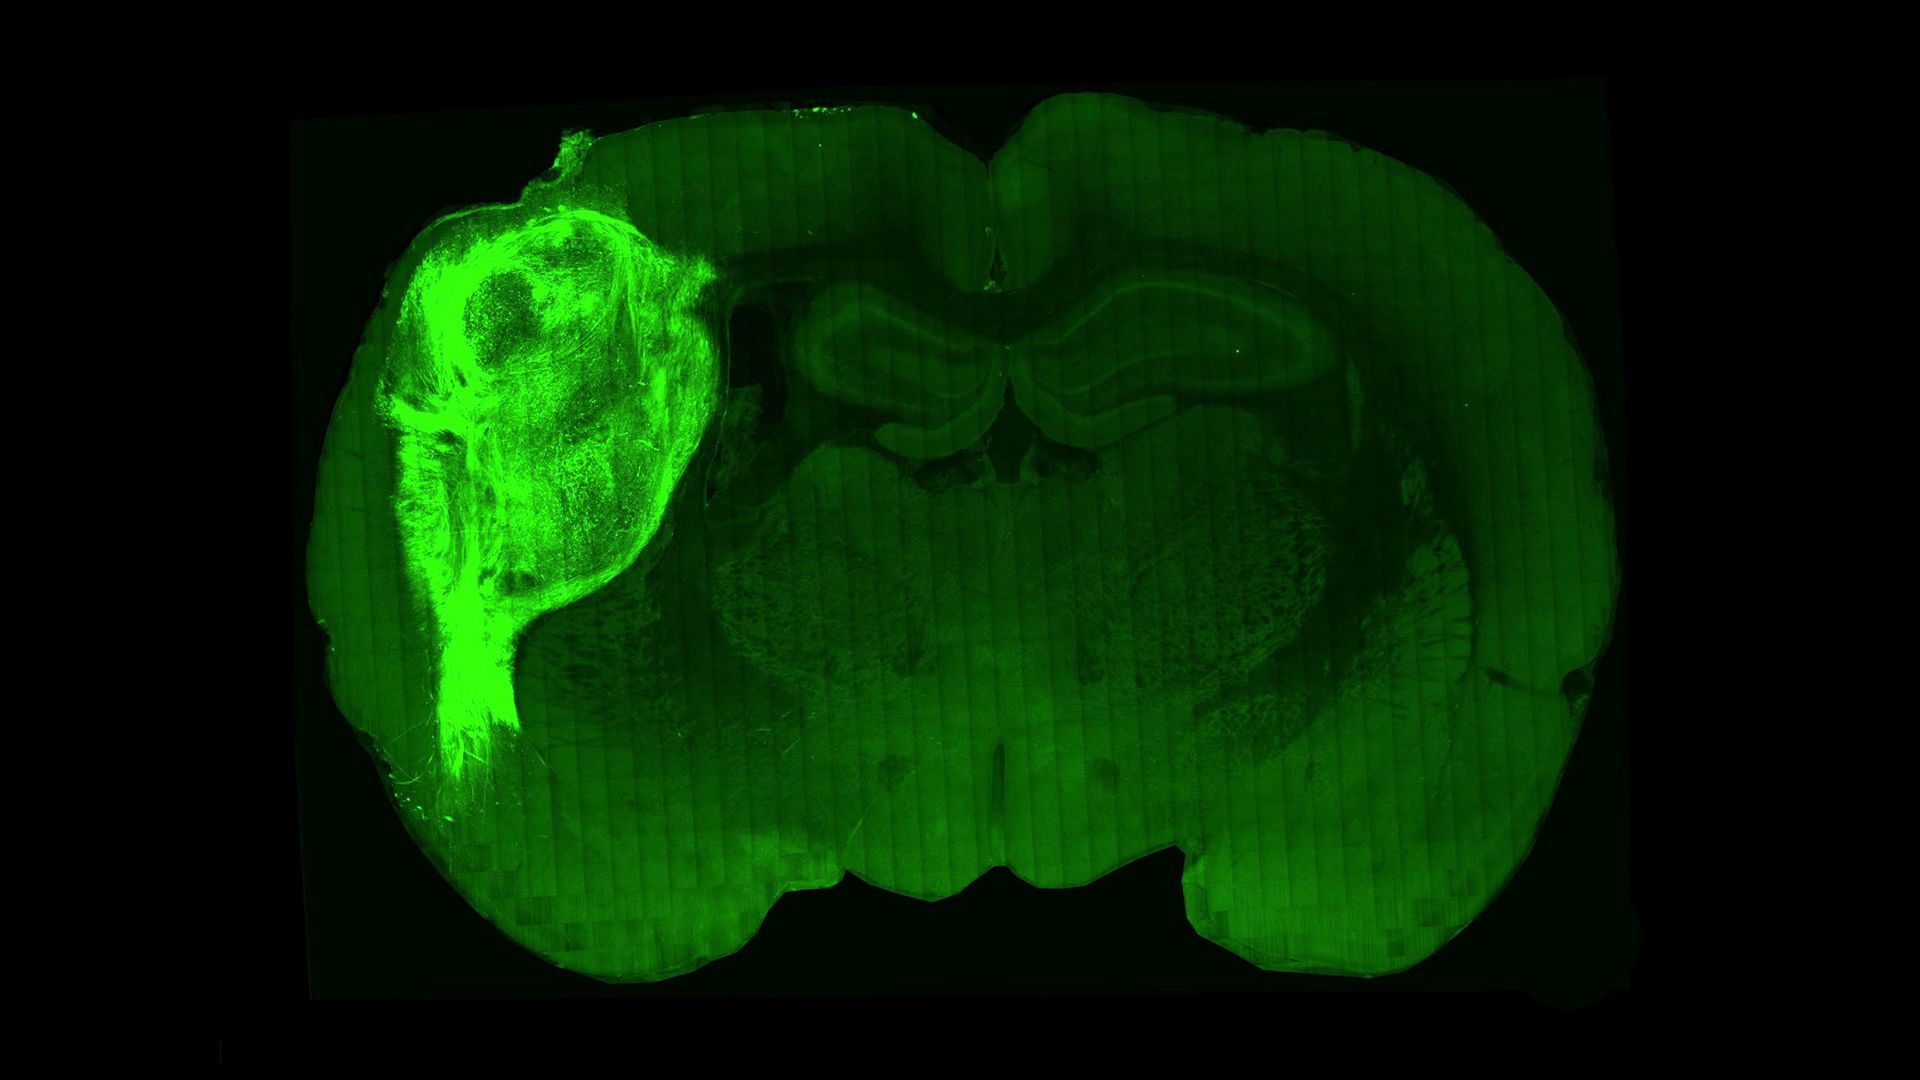

Human cells transplanted into rat brains could offer new insights on diseases

A transplanted human organoid labeled with a fluorescent protein in a section of the rat brain. Credit: Stanford University